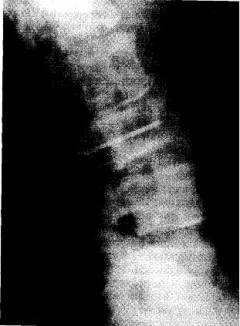

- Рентгенография костей метод рентгенологического исследования костей. Цель выявить участки поражения костей и подтвердить диагноз «миеломная болезнь». Для того чтобы получить полное представление о степени поражения делают снимки с передней и боковой проекции.

Изменения на рентгене при миеломной болезни:

- признаки очагового или диффузного остеопороза (снижение плотности костной ткани)

- «дырявый череп» – круглые очаги разрушения в черепе

- плечевые кости – отверстия в виде сот или «мыльных пузырей»

- ребра и лопатки имеют отверстия, «изъеденные молью» или «сделанные пробойником»

- позвонки сдавливаются и укорачиваются. Они приобретают вид «рыбьих позвонков»

При рентгенографии запрещено использование контрастных веществ. Так как йод, входящий в их состав, образует нерастворимый комплекс с белками выделяемыми миеломными клетками. Это вещество сильно повреждает почки.